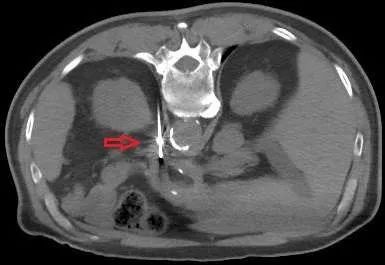

肾上腺腺瘤微波消融术中

图3. 左侧肾上腺腺瘤(红圈)。

图4. 微波针穿刺到位。